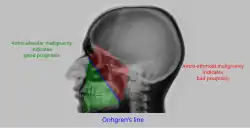

Malignancy |

![]()